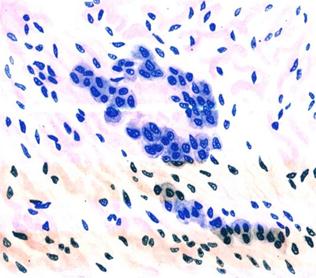

Рис. 41. Ревматическая гранулема Ашоффа — Талалаева в строме миокарда.

Гранулема состоит из гистиоцитов с базофильной цитоплазмой (а), в центре гранулемы очаг фибриноидного некроза соединительной ткани (б

Рис. 2. Микропрепарат миокарда при ревматизме: среди гипертрофированных мышечных волокон располагается крупная ревматическая гранулема. Окраска гематоксилином и эозином; ×90.